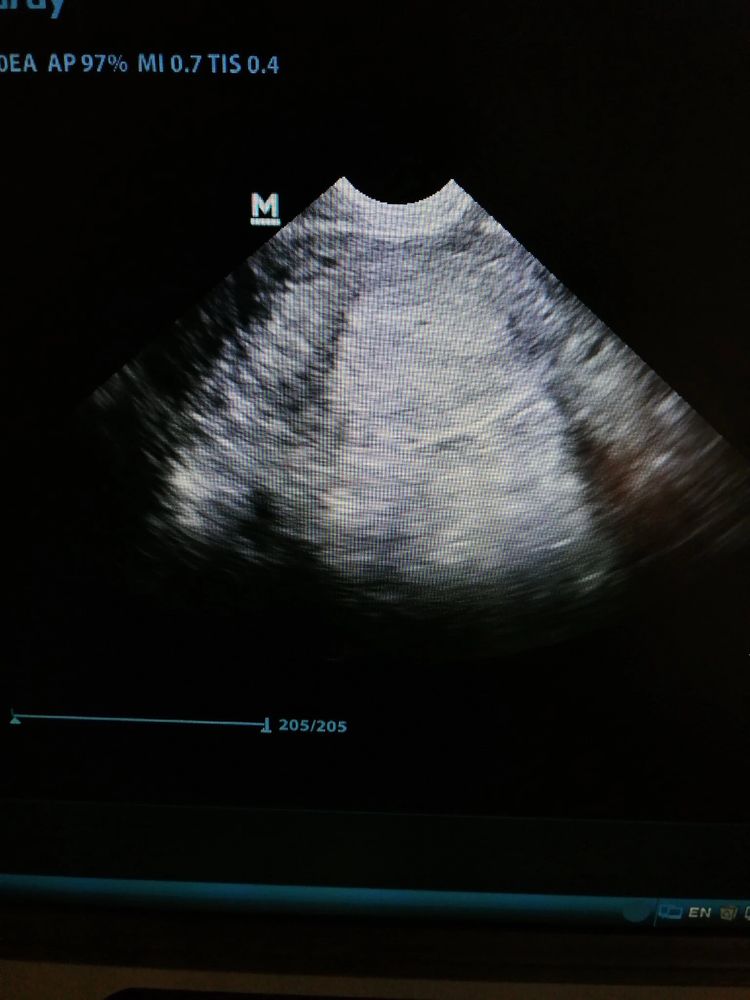

Плодное яйцо ,сгусток

Плодное яйцо 2 мм

Я пришла в ЖК и мне сказали что это врач тупой он типо слишком приблизил увеличил и что это просто был какой то сгусток а он перепутал его с плодным яйцом

Тогда я ничего не стала делать я просто поняла хорошо я не беременна, и потом у меня пошли месячные через какое то время, и все я забыла об этом , но сейчас когда я планирую я наткнулась на это узи и думаю что это все таки тогда было, может быть какая то замершая беременность